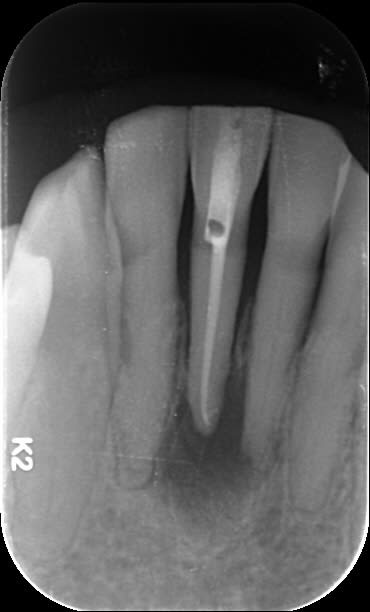

Je soigne une patiente de 88 ans, plutôt en bonne santé qui présentait une infection apicale sur 31 il y a 1 an. Voussure vestibulaire, pas vraiment douloureuse.

Bref je dévitalise, bonne irrigation et la voussure disparaît rapidement.

Je laisse cicatriser tranquillement sauf que 1 an près, c'est pire.

Ci joint le cône beam

A la base je pense qu'il y avait un second canal en lingual. Regarde les coupes horizontales tu devrais le trouver ou au moins l'imaginer. Sur les coupes sagittales, le canal que tu as obture est deporte en vestibulaire, c'est une bonne indication. Sur la retro tu vois bien les deux racines de l'incisive latérale, tu trouves en general 2 canaux sur la centrale dans ce cas la.